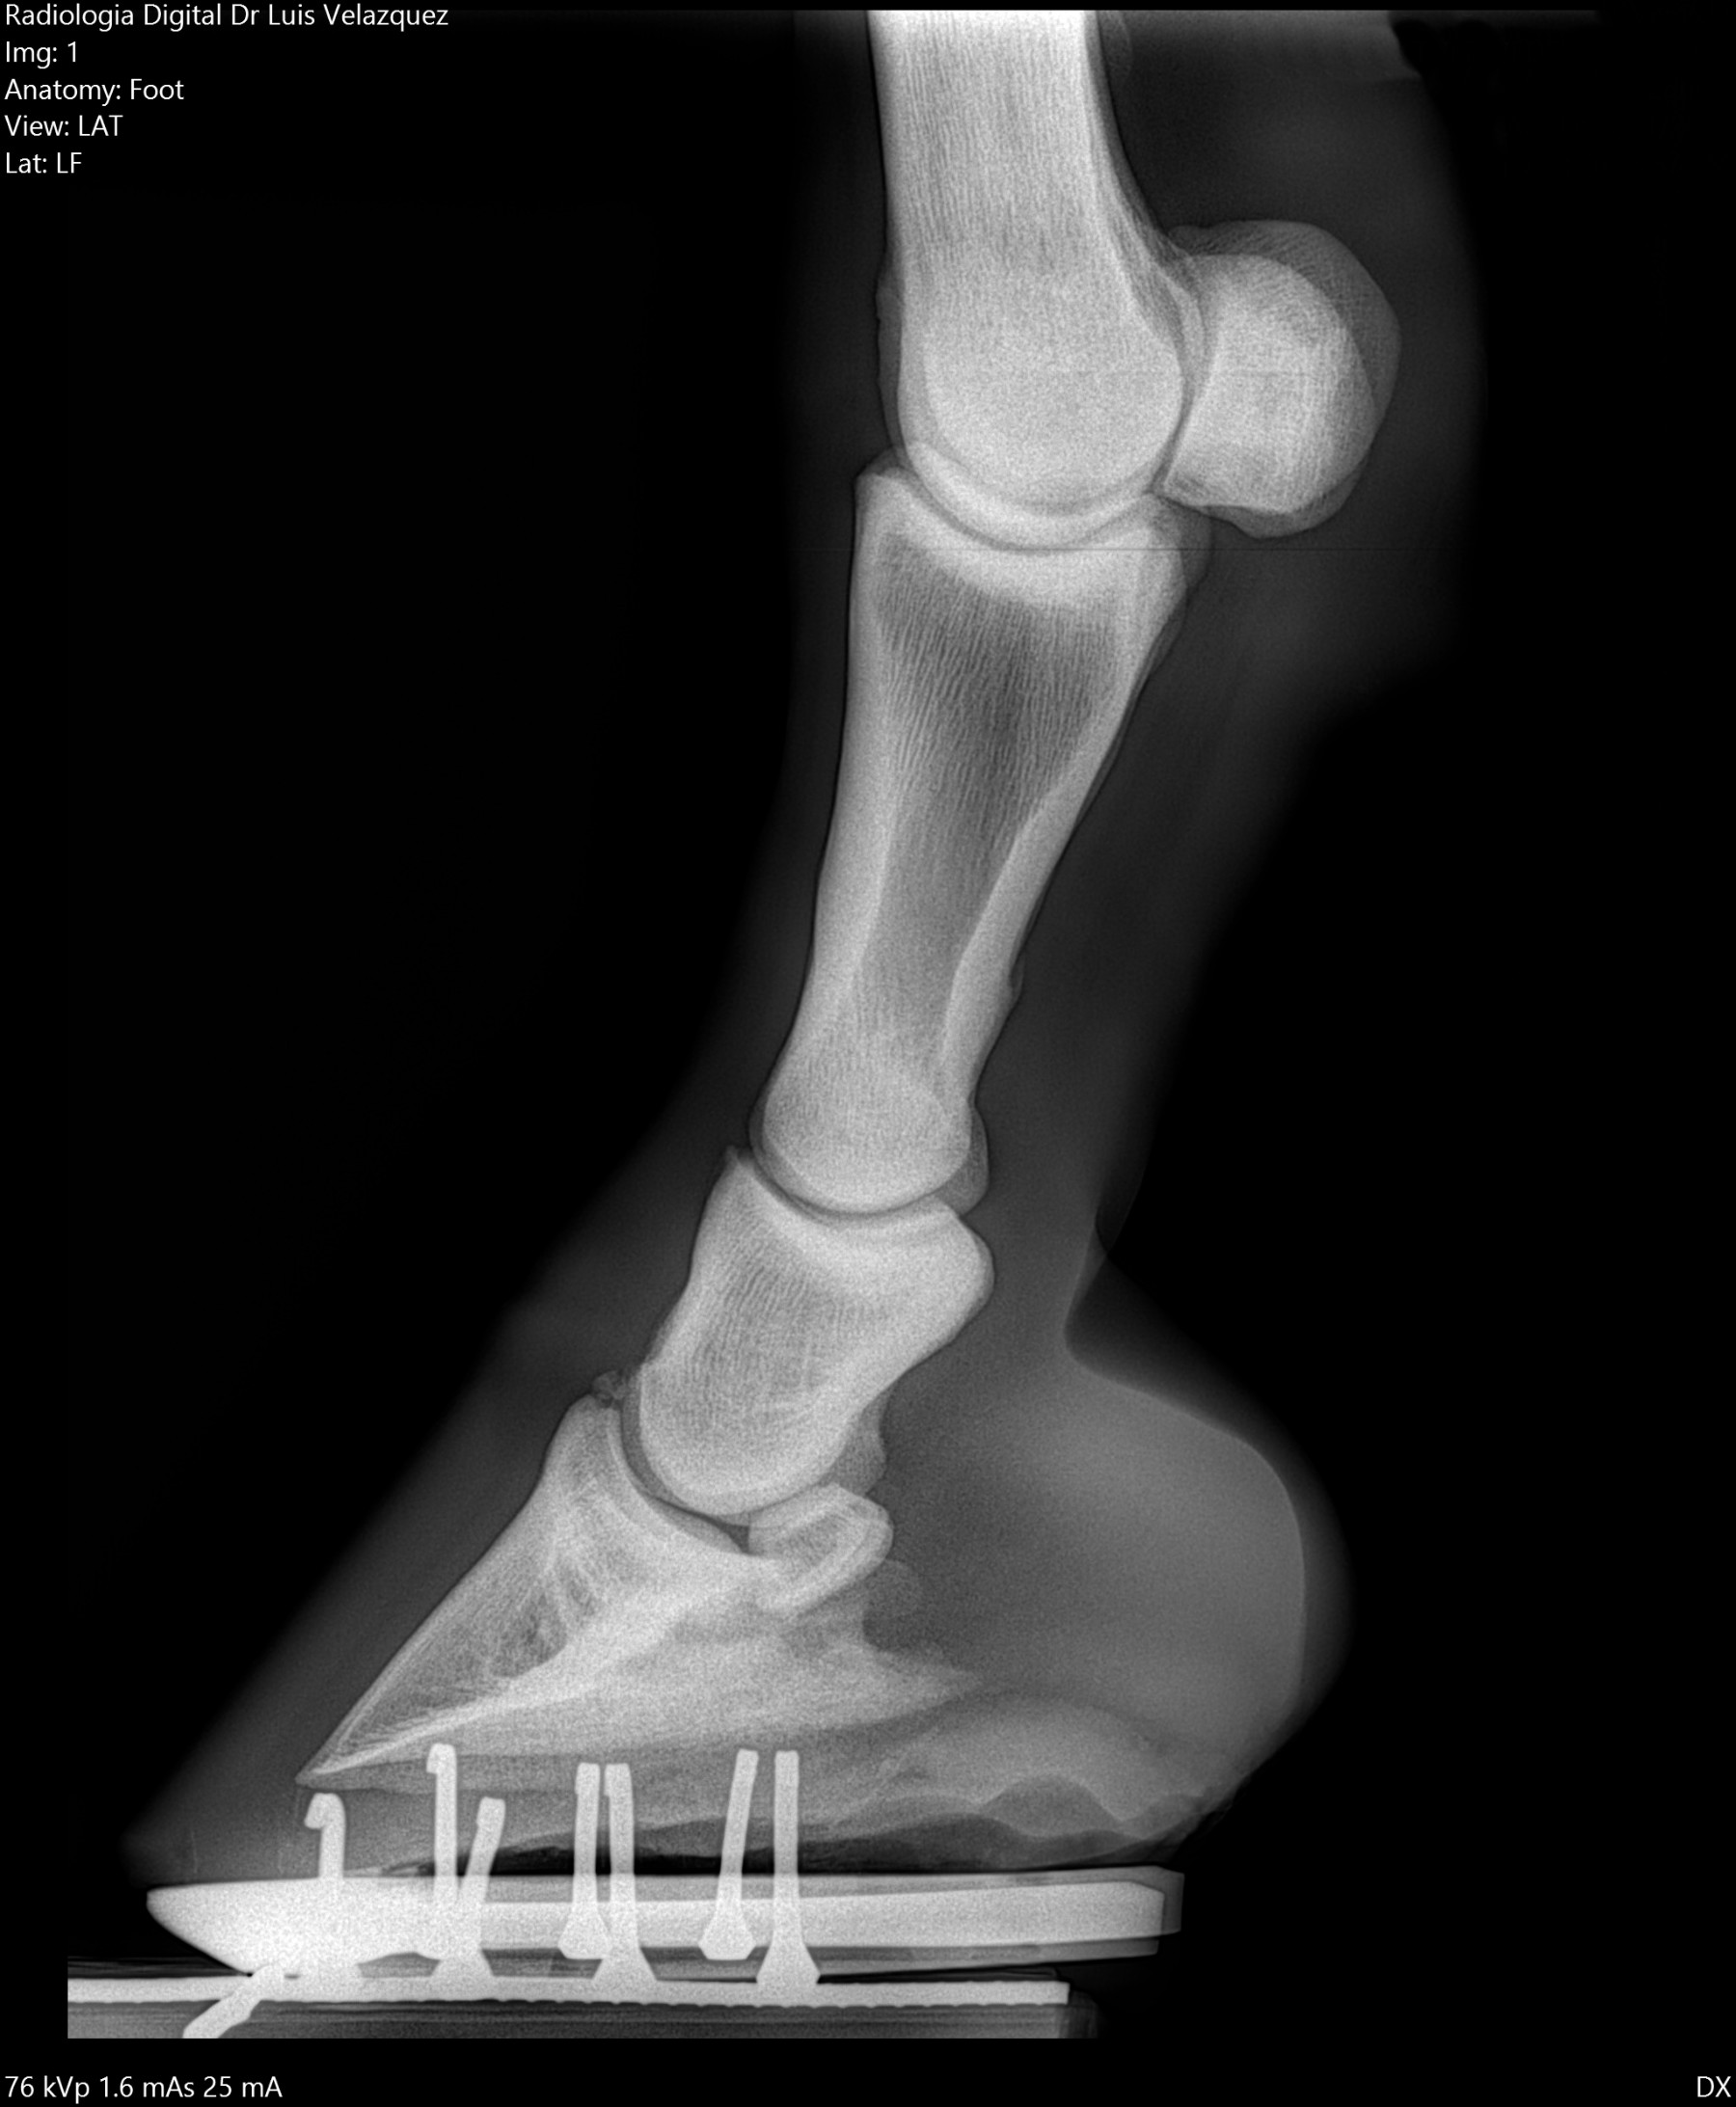

Radiología Digital como Herramienta Complementaria en el Dictamen de Bienes Muebles

Cambios Térmicos en las Extremidades de Caballos,

Asociados a Golpes y su Evaluación por Termografía.

Los caballos de salto, en competencia, pueden derribar obstáculos y lastimarse. Si se golpean, no siempre claudican. Considerando al calor como un signo de inflamación, se evaluaron los cambios térmicos de 6 áreas de las extremidades torácicas y pelvianas de 23 caballos de salto en nivel de competencia de 1.05 a 1.60 m de altura, por medio de termografía durante 4 días de competencia (N=2208 áreas).